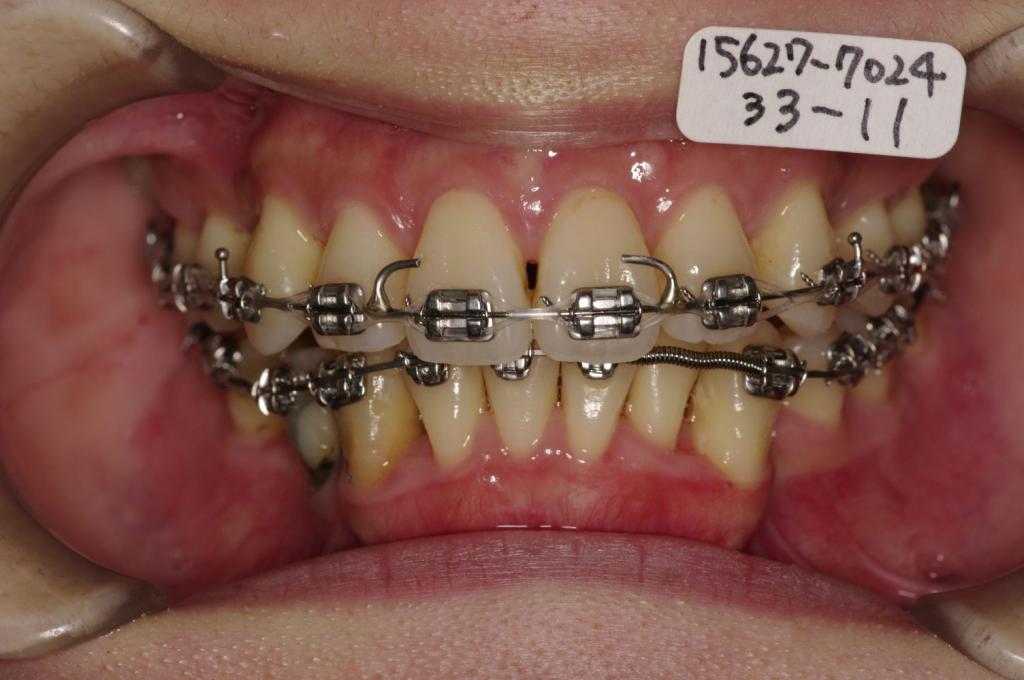

装置の種類及び治療法 診断:下顎右側第二小臼歯先天欠如 叢生 上下顎前突

治療方法および装置:マルチブラケット装置

High pull J-hook headgear

抜歯:右上84 /左上4

右下E /左下48

欠損歯:右上 /左上8

右下85 /左下

治療期間:19ヶ月

装置写真

治療前

歯欠損の矯正治療前口内写真NO.142